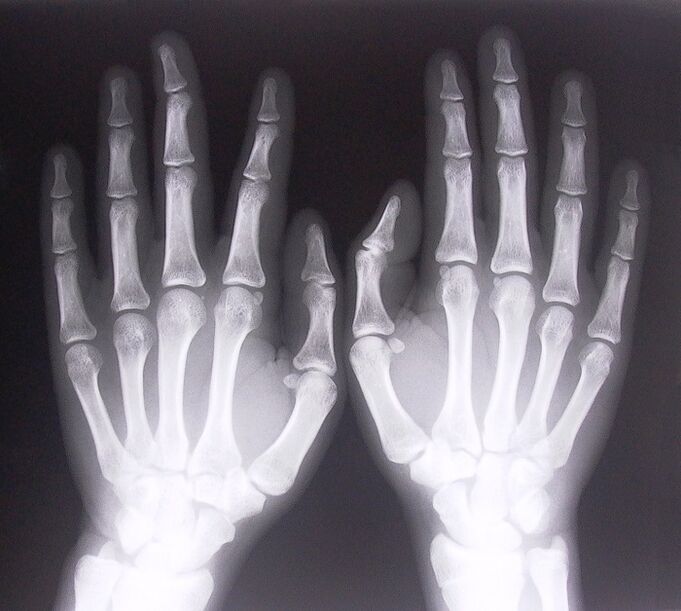

- Ligamentitis estenosatzailea. Gaixotasunaren kausa identifikatzeko, beharrezkoa da erradiografia bat egitea. Sintomak tipikoak dira: eskuaren mugimendu mingarria, ahurraren begizta. Gainera, luzapenean, klikak entzun ohi dira.

Hatzetako artikulazioetako mina tratatzen hasteko, behar bezala zehaztu behar duzu zer gaixotasun eragin dituen. Besoak makurtzean artikulazioetan mina sentitzen duen pertsona batek zer gaixotasun eragiten duen zehazteko, medikuek honako prozedura hauek egitea gomendatzen dute:

- Hartu x izpiak.